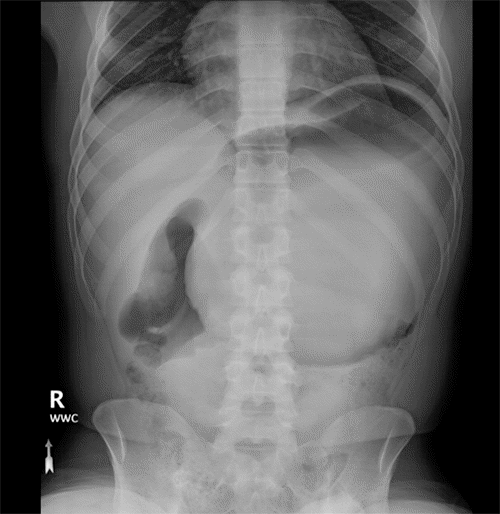

A chest X-ray revealed a mass-like opacity in the left mid abdomen, extending to the right paraspinal region and causing displacement of bowel loops inferiorly and to the right side (Figure 1). This prompted further evaluation with a computerized tomography (CT) scan, which indicated findings suggestive of gastric volvulus (likely mesentero-axial) with perforation, along with a large amount of pneumoperitoneum and free fluid (Figure 2).

Figure 1. Mass-like Opacity in Left Upper Quadrant. Published with Permission